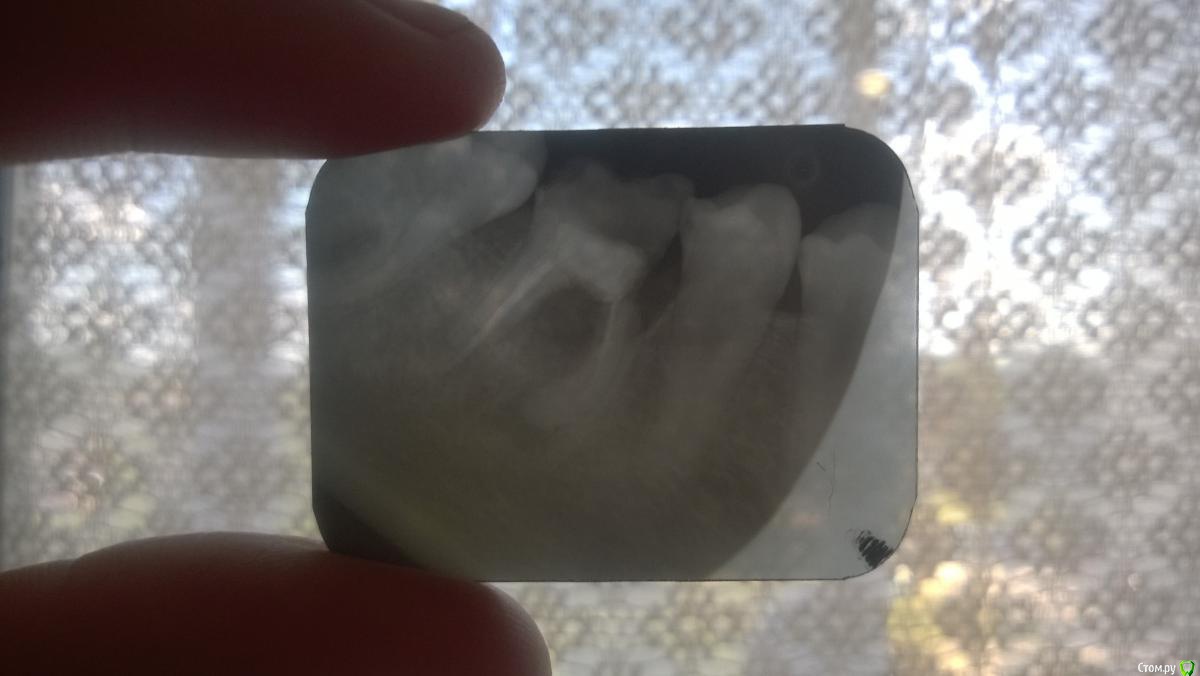

Dimakozak Опубликовано 19 июля, 2017 Поделиться Опубликовано 19 июля, 2017 Помогите сходила к врачу потому что выпала платная пломба сказали сделать снимок я его сделала и меня разочаровали что надо удалять зуб можно что либо ещё сделать Ссылка на комментарий

AndyAndy Опубликовано 19 июля, 2017 Поделиться Опубликовано 19 июля, 2017 Удалять Ссылка на комментарий

red_butler Опубликовано 20 июля, 2017 Поделиться Опубликовано 20 июля, 2017 А после этого можно будет его как не будь восстановитьКоронкой на имплантате Ссылка на комментарий